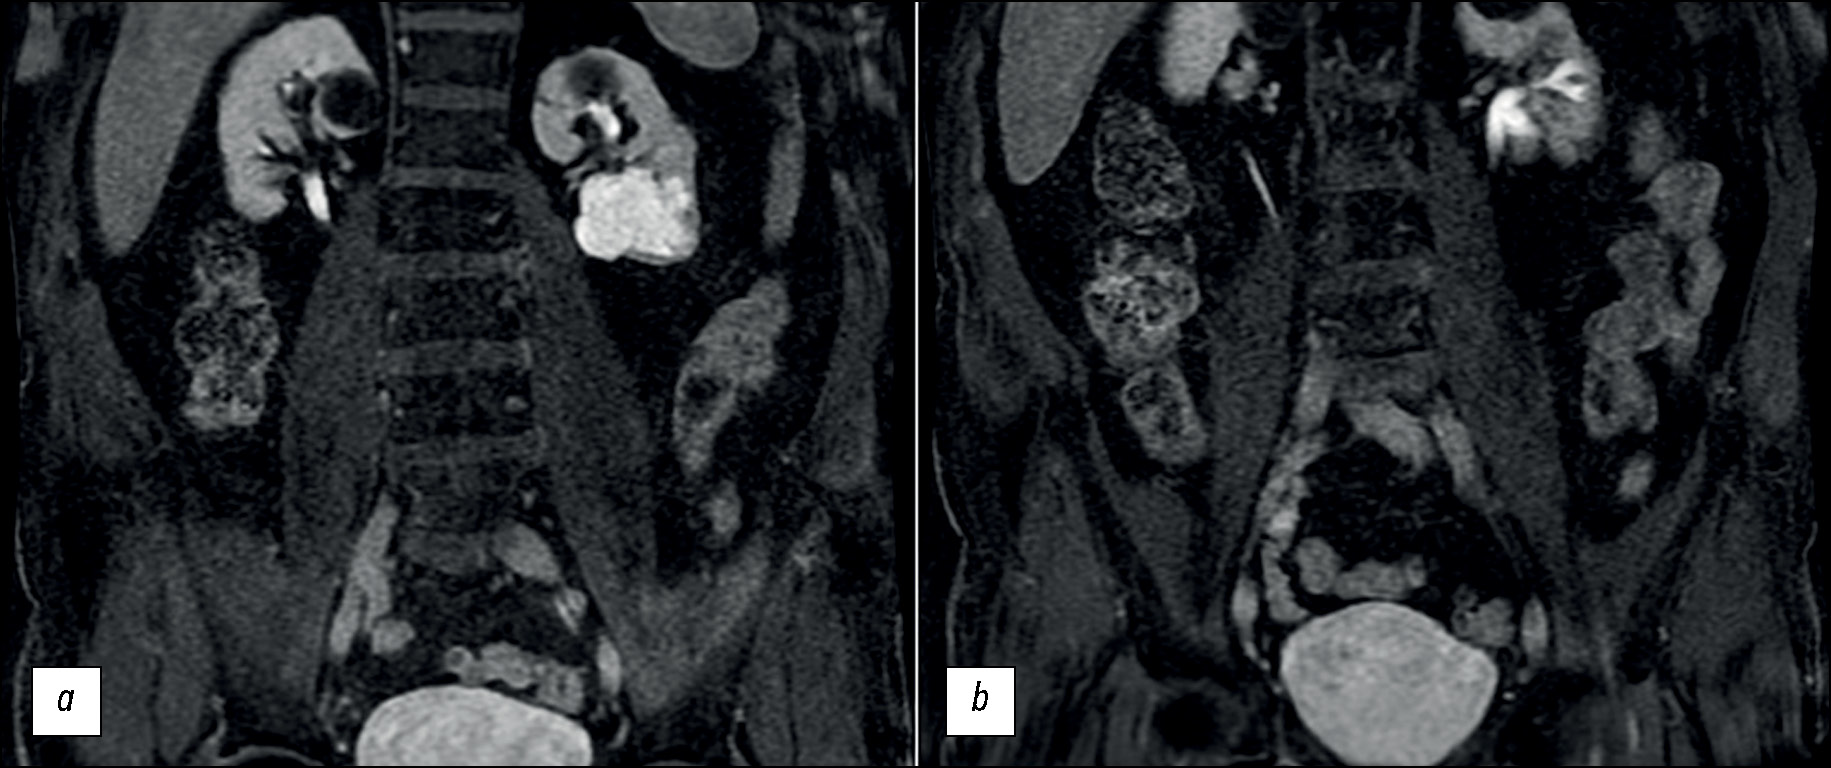

Рис. 3. Обработанные изображения, полученные методом двухэнергетической компьютерной томографии, корональная плоскость. На цветокодированных картах распределения йода (a, b) поглощение йода выделительной системой, включая дивертикул чашечки почки, представлено ярко-желтым цветом. На рисунке b сигнал от йода в области кист отсутствует.

Чтобы более точно охарактеризовать образование и подтвердить гипотезу о наличии дивертикула чашечки почки, которая была выдвинута по результатам КТУ, была проведена магнитно-резонансная урография (МРУ). В средне-нижней части левой почки было обнаружено дольчатое образование, сообщающееся с чашечно-лоханочной системой через узкий канал. В частности, наличие сообщения было подтверждено в экскреторной фазе, когда кистовидная полость заполнилась контрастным веществом. Результаты исследования указывали на наличие дивертикула чашечно-лоханочной системы почки (рис. 4, рис. 5).

Рис. 5. Магнитно-резонансная урография, коронарные срезы, T1-взвешенные изображения в режиме жироподавления в отсроченной фазе после введения контрастного вещества. Два образования, расположенные в верхнем полюсе обеих почек, представляют собой кисты. (На двух последующих изображениях визуализировалось заполнение дивертикула контрастным веществом, а его воронкообразный канал сообщался с чашечно-лоханочной системой почки).